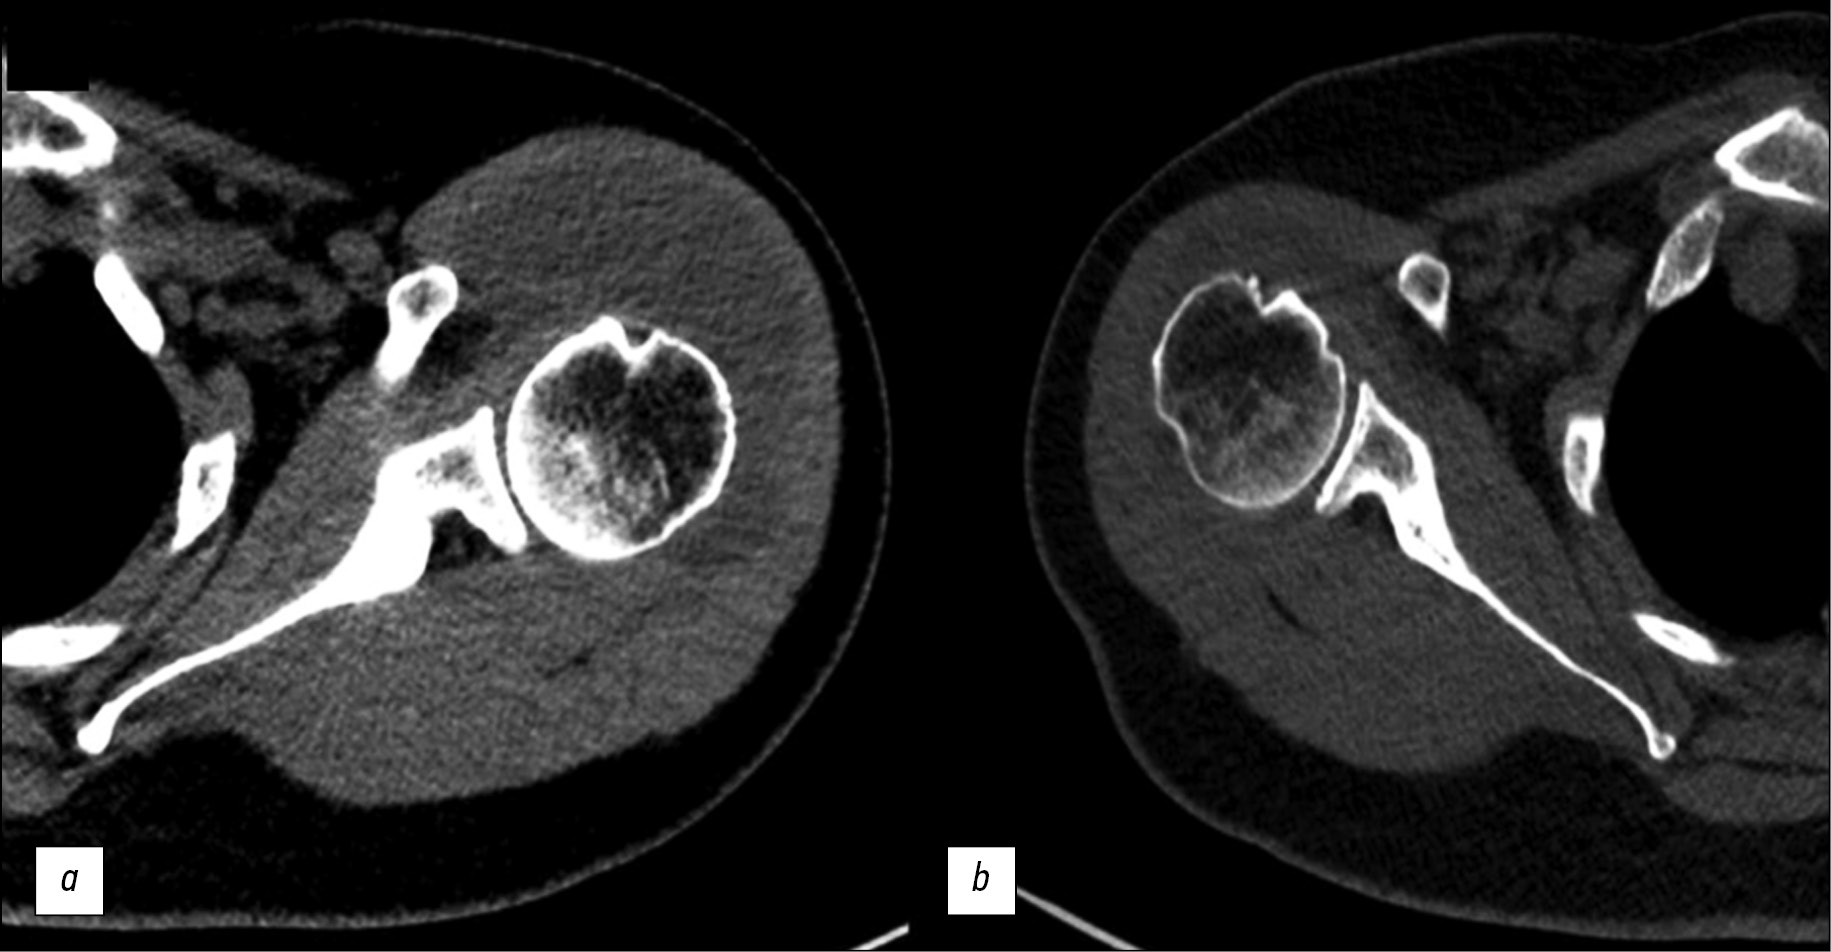

Noncontrasted CT images of the shoulder joints obtained with Somatom Drive (Siemеns Healthineers, Germany) with a 0.625-mm slice thickness showed large lens-shaped hypodense structures on both sides in the subacromial and subdeltoid bursae (Fig. 3):

- On the left side: 7.5 × 4 × 9 cm; the mass is bigger than the MR evaluation (7.7 × 2.5 × 5 mm)

- On the right side: 4 × 1.4 × 4 cm

Fig. 3. Computed tomography of the shoulder joints, axial sections: a - left shoulder joint; b — right shoulder joint.

Their structure appeared homogeneous in the CT images, without calcification or solid inclusions; the structure density was ~35 HU. Reactive lymphadenopathy associated with the underlying disease was observed in the axillary areas.